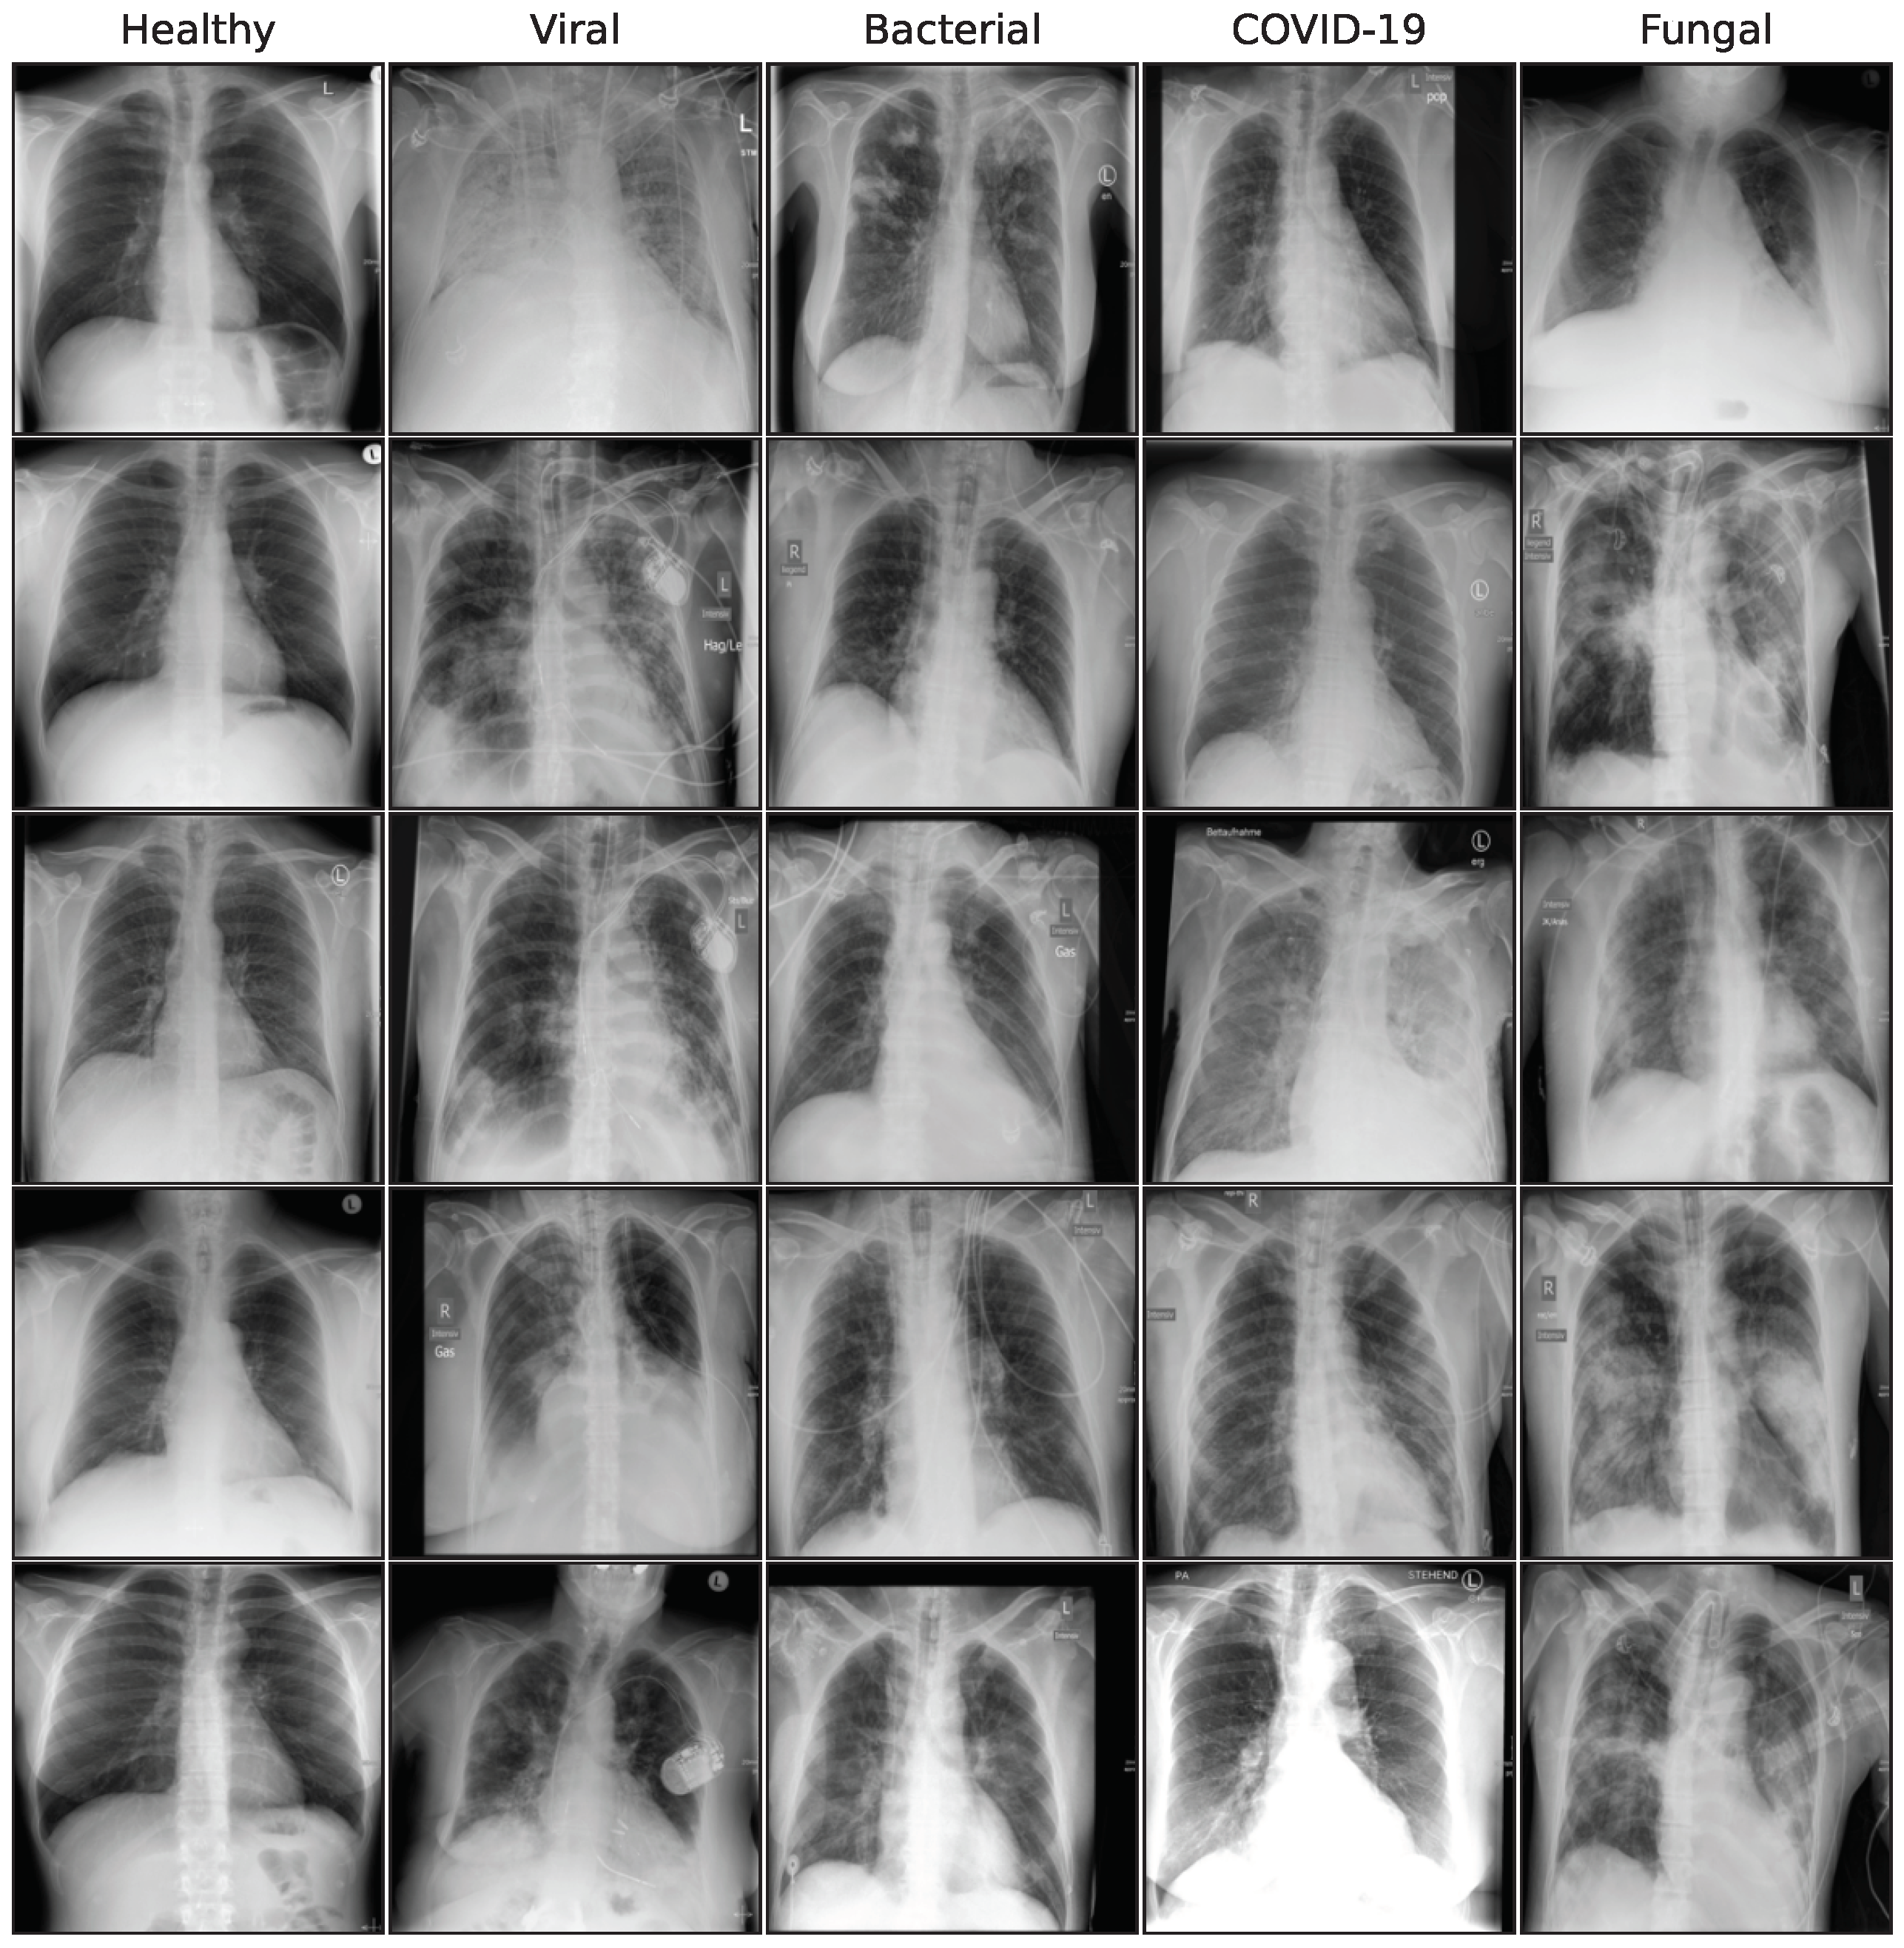

3.2. Image Synthesis

This subsection describes the generative models used in this work. We utilize a special GAN model, a Denoising Diffusion Probabilistic Model (DDPM), and 3 different fine-tuning approaches for a Stable Diffusion [34] model: standard fine-tuning, Low-Rank Adaption (LoRA), and DreamBooth. Our aim is to compare the performance of a GAN model to more recent diffusion-based architectures, building on the GAN proposed in Schaudt et al. [35]. Figure A2 in the Appendix A shows a collection of synthetic images for all generative models.

Figure A2. Sample synthetic images from all classes and methods.

Bioengineering 10 01421 g0a2